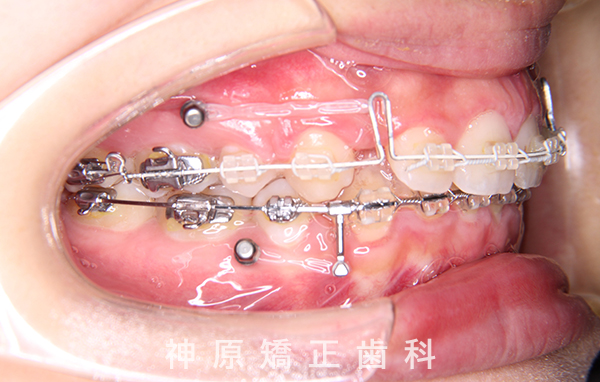

- 治療に用いた主な装置

-

上顎:唇側矯正装置

下顎:唇側矯正装置

歯科矯正用アンカースクリュー - 抜歯 / 非抜歯

マルチブラケット装着1年後

口元の突出感を改善するために小臼歯の抜歯が必要と判断しました。抜歯スペースを活用し、前歯を可能な限り後方へ移動させるため、上下に矯正用アンカースクリューを使用する計画です。患者様とご家族に十分な説明を行い、治療ゴールに同意を得た上で矯正治療を開始しました。矯正治療の結果、側貌はE-lineに調和したバランスの良い仕上がりとなりました。